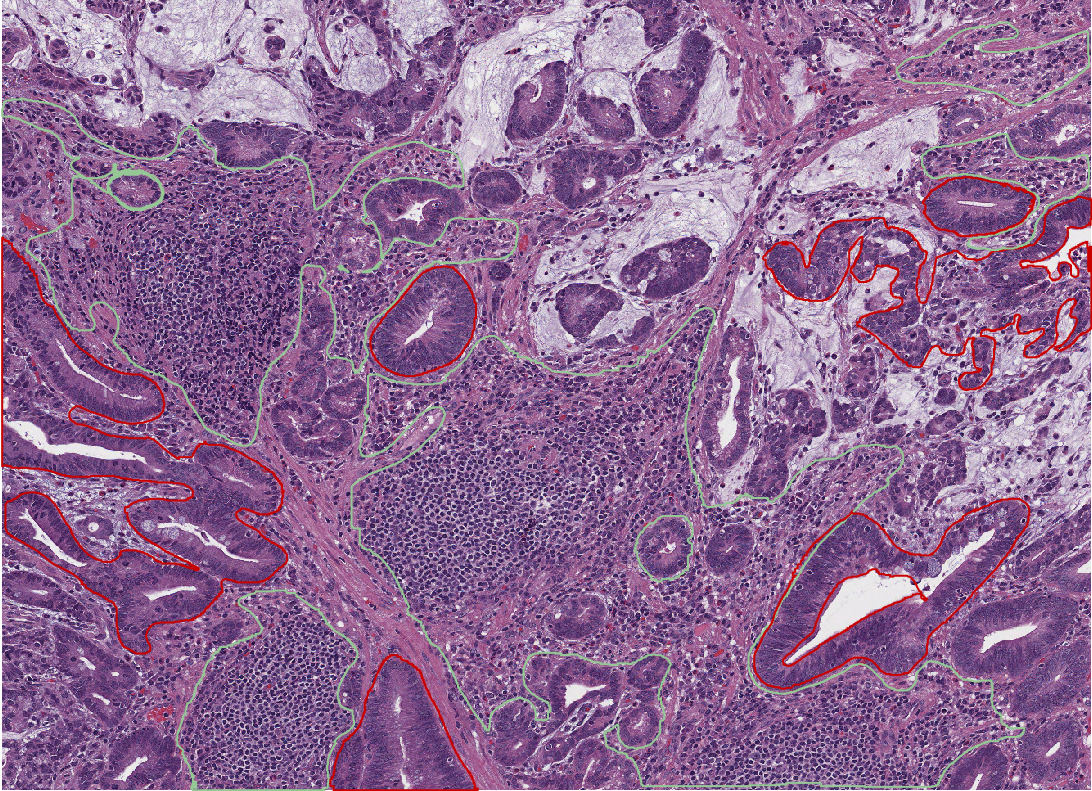

annotations classified

Fig. 2.16 – The annotations are classified as tumor or stroma.